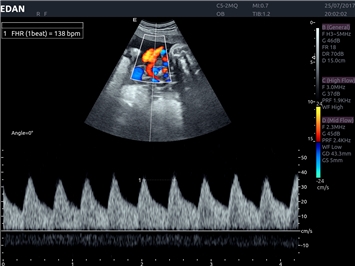

EDAN Acclarix LX4 представляет собой инновационную ультразвуковую систему, построенную на усовершенствованной платформе Acclarix. Сочетание высокого качества визуализации с интеллектуальным рабочим процессом делает эту систему оптимальным выбором для клиник, ценящих эффективность и экономичность.

• Тканевая допплеровская визуализация (TDI)

Импульсно-волновой допплер:

Да